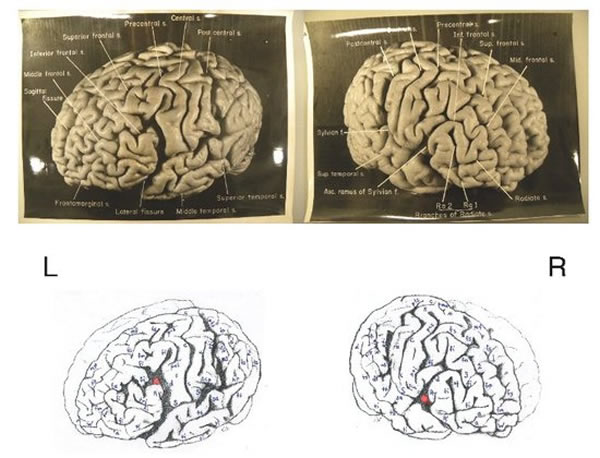

阿尔伯特-爱因斯坦大脑皮层的初步描述和分析

爱因斯坦大脑中异于常人的位置标识

正如佛罗里达州立大学的声明所述,大多数的照片、样本和幻灯片离开公众视线超过了55年。幸运的是最近发现了一些而且现在能够在国家健康和医学博物馆中看到它们。确切的说通过对14张照片的研究,福尔克和她的同事们能够更加深入的了解爱因斯坦的大脑。他们的发现非常的惊人。福尔克在比较了科学文献中描述的85位其他人类大脑之后称:“尽管爱因斯坦大脑的总体尺寸和非对称性是正常的,前额、体感、主运动皮质、颞部和额枕皮质是完全不同的。”